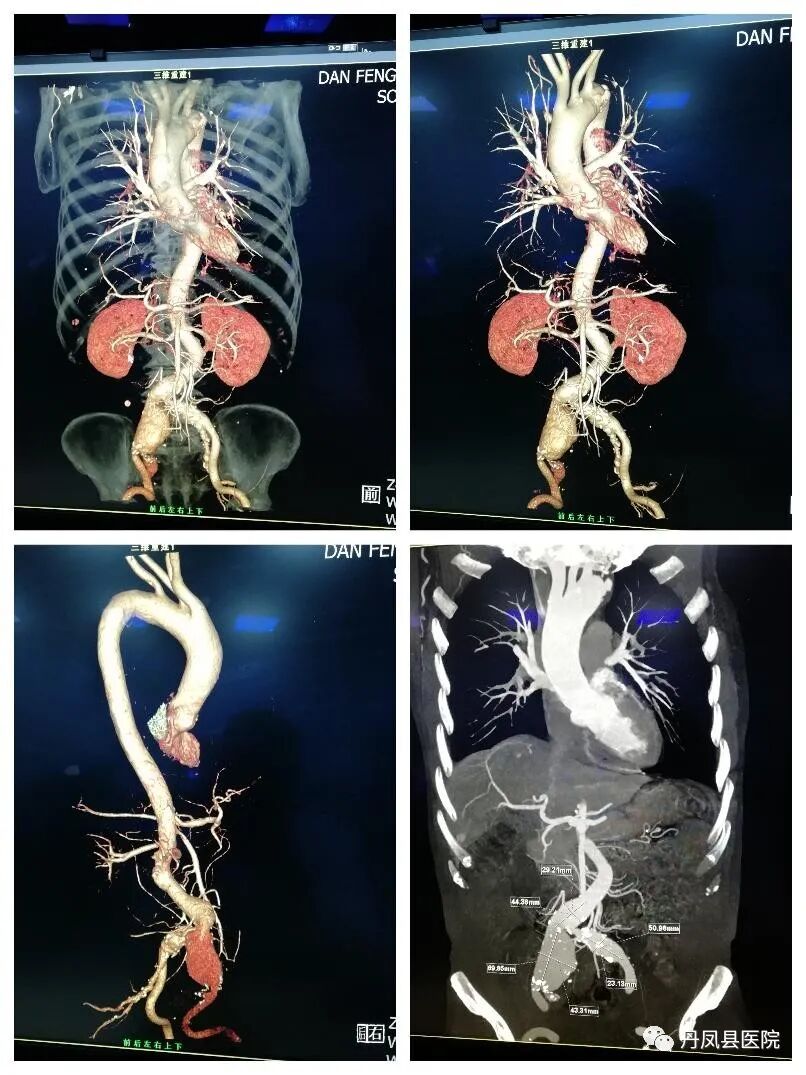

![]()

胸腹主动脉CT血管造影(CTA)

胸腹主动脉CT血管造影(CTA)是一种有效诊断主动脉夹层的重要影像学方法,准确性、安全性高及无创等优点为诊断主动脉夹层的常规方法之一,准确判断夹层的类型、波及范围。